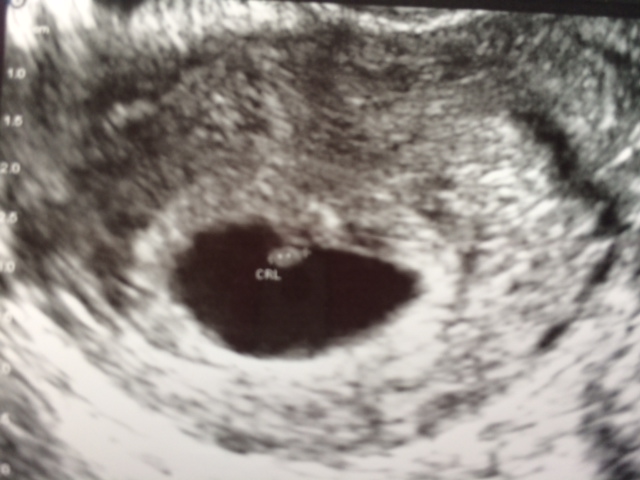

I went yesterday for my early ultrasound - 6 weeks 1 day and the baby was attached in the middle at the top with the yolk sac directly beneath it. The pic with the yolk sac is hard to tell because everything was so squished but it really was not swayed one side or the other. does anyone have any experience with Ramzi when the baby implants smack dab in the center? My first two boys were clearly in the right bottom corner, so this is throwing me off! And of course I am dying to know and willing to study every little detail!!Attachment 15570Attachment 15571